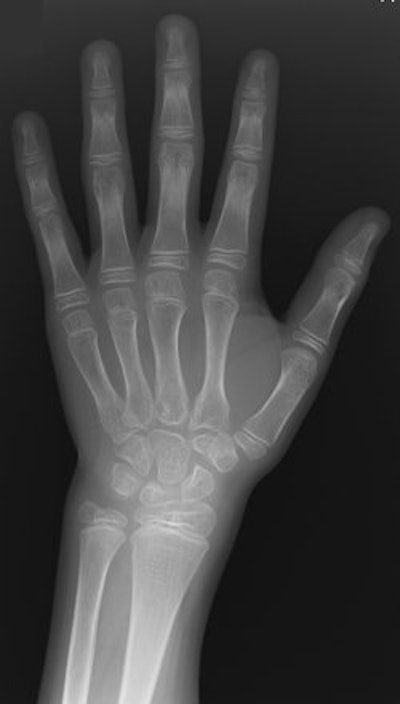

Another characteristic aspect of CACP syndrome is visible in the hands, in the squaring of the metacarpal and phalangeal heads.

| Fourteen-year-old boy with camptodactyly-arthropathy-coxa vara-pericarditis (CACP) syndrome. Dorsopalmar radiograph of left hand illustrates that presence of camptodactyly may not always be obvious from radiographs. Arthropathy in CACP syndrome may be associated with periarticular osteopenia. Note absence of erosive change. Although this appearance is consistent with early juvenile idiopathic arthritis, squaring of metacarpals and phalanges (seen in CACP syndrome) helps to differentiate two conditions. Amaka OC, Woo P, Prieur A, Hasson N, Hall CM, "Camptodactyly-Arthropathy-Coxa Vara-Pericarditis Syndrome Versus Juvenile Idiopathic Arthropathy" (AJR 2005; 185:522-529). |